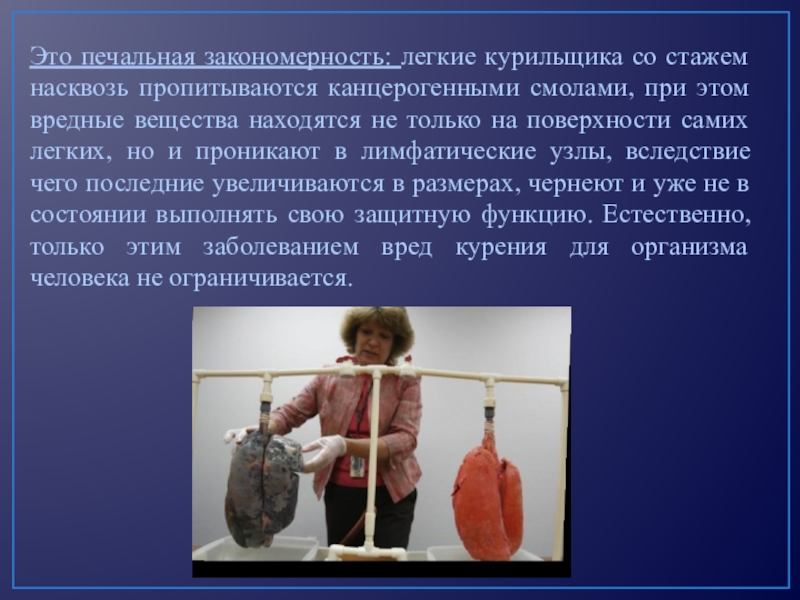

Здоровый образ жизни: Влияние курения